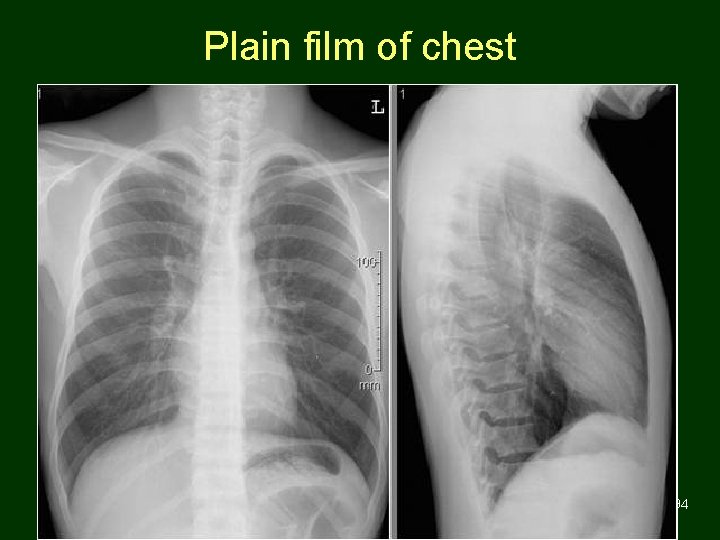

Plain film of chest 93

Plain film of chest 94

Plain film of chest 95

Plain film of chest 96